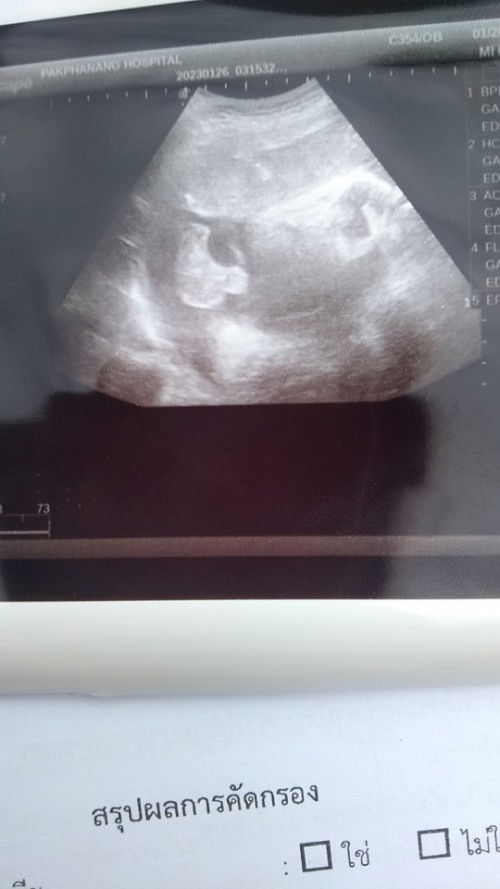

น้องนิวเคลียร์มารายงานตัวแล้วคับ💕 💗 ชื่อจริง : ด.ช.ธนวัฒน์ ซิวไฝ (เจริญด้วยทรัพย์) 🤴ชื่อเล่น : น้องนิวเคลียร์ ⚧ เพศ : ชาย 🗓 เกิด : วันจันทร์ 🐇 ปี : ปีเถาะ 🕰 เวลา : 14:38 am. ⚖️ น้ำหนัก : 3,500 kg. 🤰🏻 อายุครรภ์ : 40w 💫 กำหนดคลอด : 27ก.พ 2566 🩺 วิธีคลอด : เหน็บยา+ดมยา+ผ่าคลอด 🏩 สถานที่เกิด : โรงพยาบาลปากพนัง 👩⚕️ทำคลอดโดย : พญ.ศวัลยา #น้องนิวเคลียร์มาแล้วคับ♥️